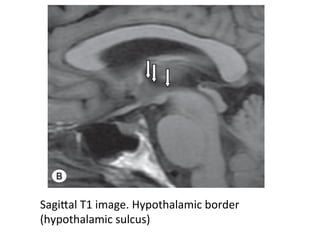

SagiTal	T1	image.	Hypothalamic	border

(hypothalamic	sulcus)

SagiTal	T2	image	demonstrates	the	structures	in	the	floor	of	the	third

ventricle:	OpHc	chiasm	(1),	pituitary	infundibulum	(2),	tuber	cinereum

(3)	and	mamillary	bodies	(4).

-The	hypothalamus	forms	the	floor	of	the	third	ventricle

and	its	side	walls	anteriorly	following	an	oblique	line

inferiorly	from	the	foramen	of	Monro	to	the	midbrain

Aqueduct.

-	It	consists	of	a	group	of	nuclei	serving	a	number

of	autonomic,	appeHte-related	and	regulatory	funcHons

for	the	body	as	well	as	controlling	and	producing	hormonal

output	from	the	pituitary	gland.

-The	hypothalamus	is	inHmately	linked	to	other	limbic

structures	and	might	be	considered	the	output	for	the

limbic	system.